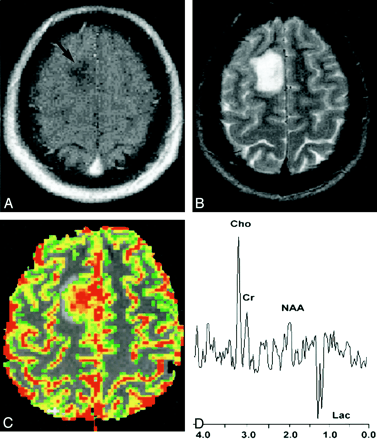

在许多中心,作为临床肿瘤成像的支柱,对比增强CT已经逐渐被磁共振成像所取代。肿瘤高强度开启T2序列[包括自旋回波和流体衰减反转恢复(FLAIR)]反映了与...